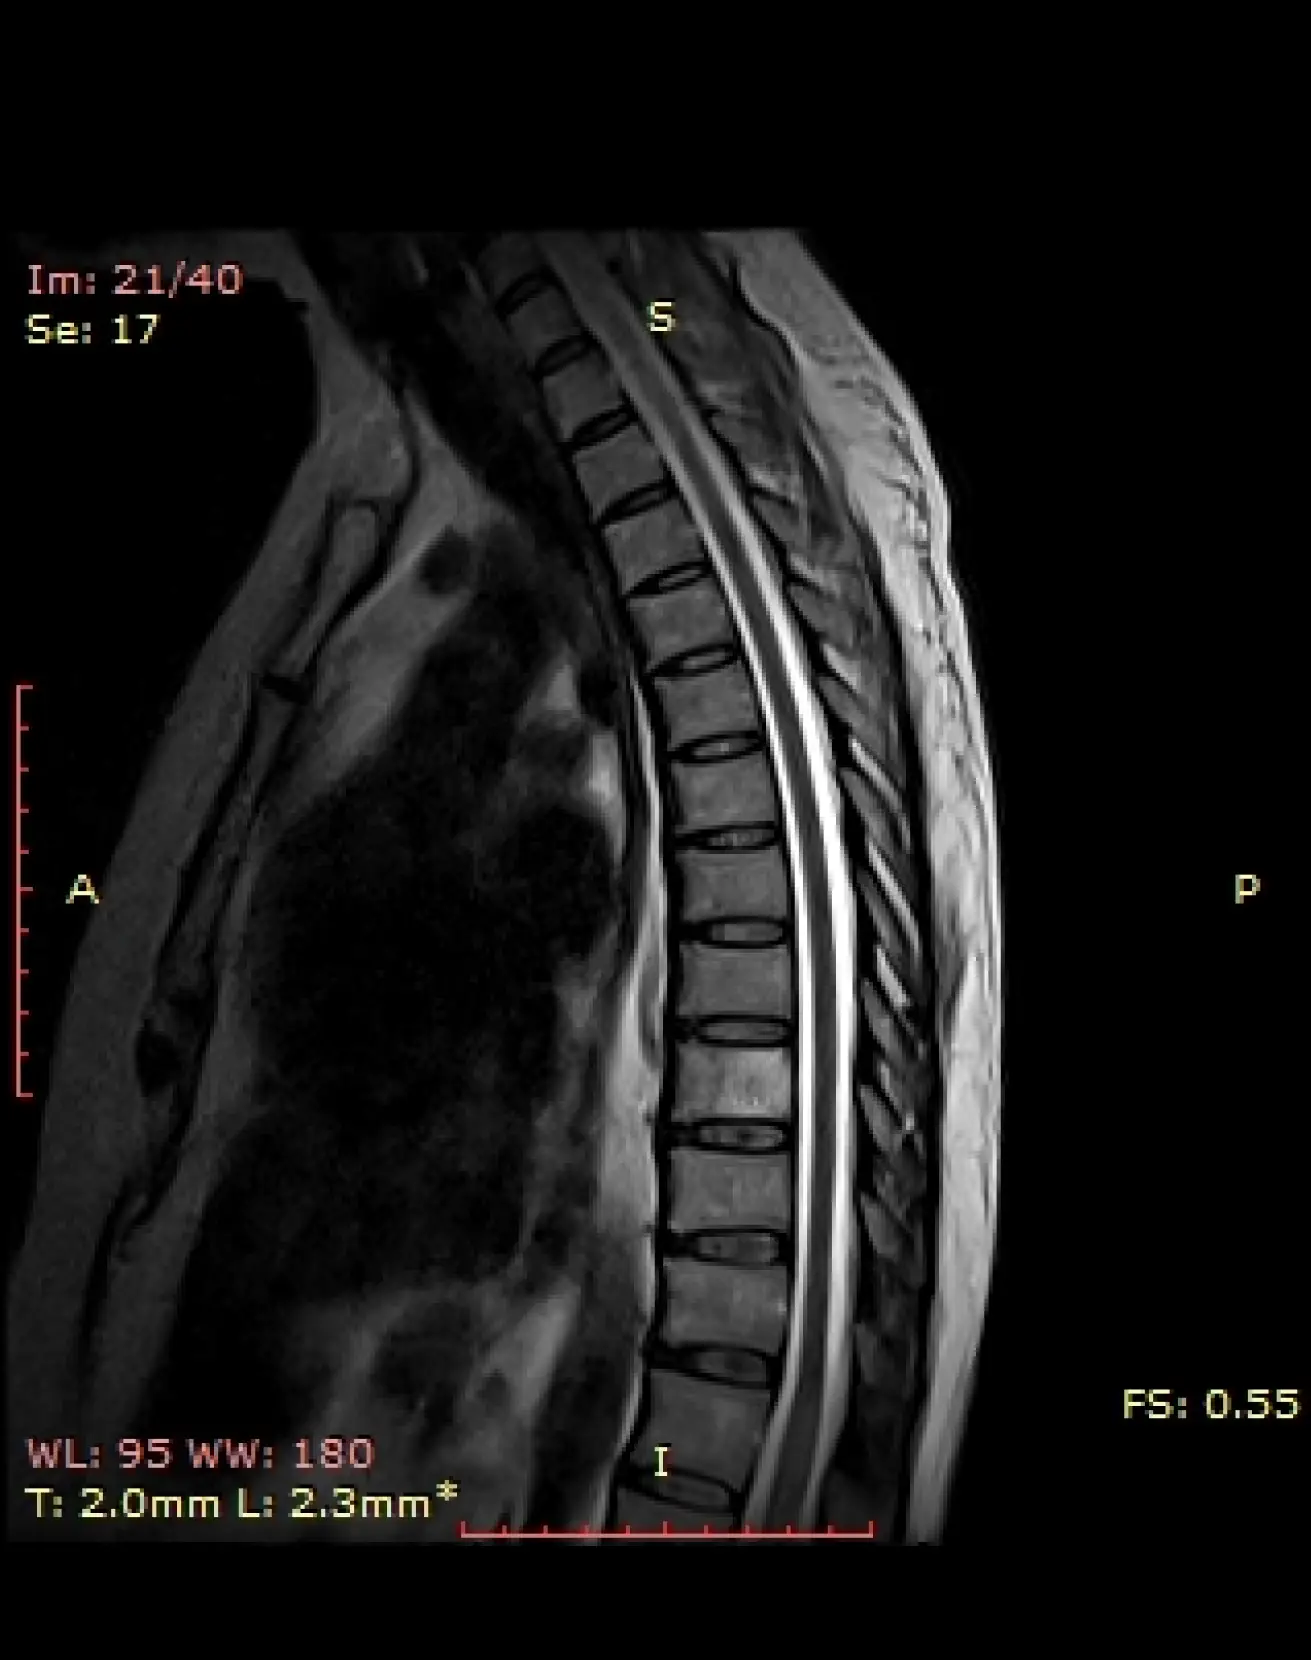

МРТ грудного отдела позвоночника

Визуализация позвонков, межпозвонковых дисков, спинного мозга, спинномозговых корешков, окружающих мягких тканей.